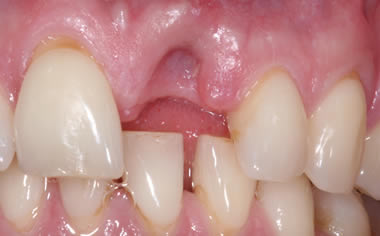

More front teeth replaced by dental implants

Case Three (4 images)